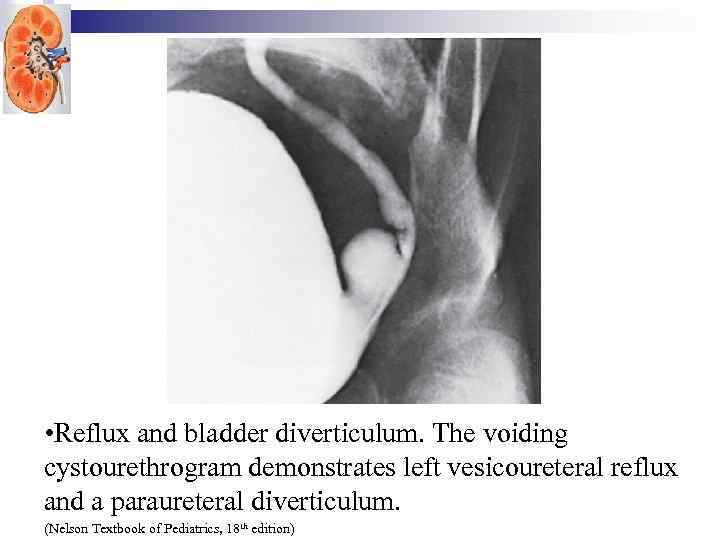

• Reflux and bladder diverticulum. The voiding cystourethrogram demonstrates left vesicoureteral reflux and a paraureteral diverticulum. (Nelson Textbook of Pediatrics, 18 th edition)

• Reflux and bladder diverticulum. The voiding cystourethrogram demonstrates left vesicoureteral reflux and a paraureteral diverticulum. (Nelson Textbook of Pediatrics, 18 th edition)